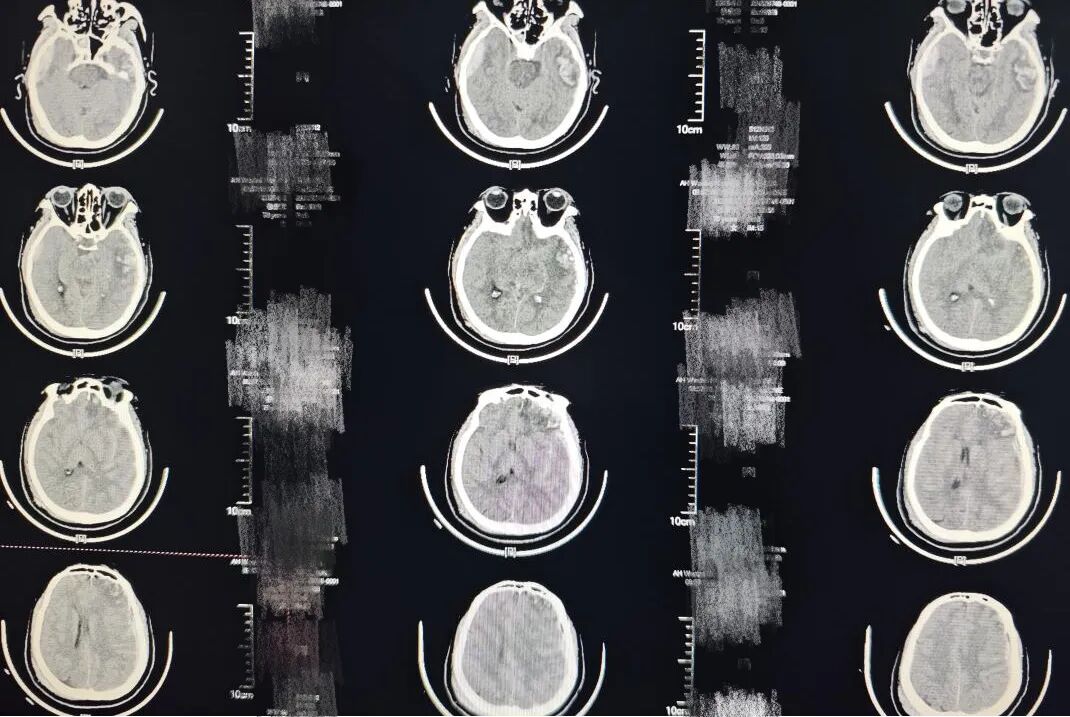

"脑疝形成、双侧血肿、多发脑挫裂伤..."接诊医生快速查看外院CT报告,每一个冰冷的医学术语背后,都是一个年轻生命正在流逝的残酷现实。

图|患者入院时影像

神经外科三病区方志强医师接到会诊通知后,即刻赶赴现场。凭借多年积累的丰富经验与敏锐的判断力,方志强医师迅速制定手术方案,果断实施脑挫裂伤加硬脑膜下腔血肿清除术+颅骨去骨瓣减压术